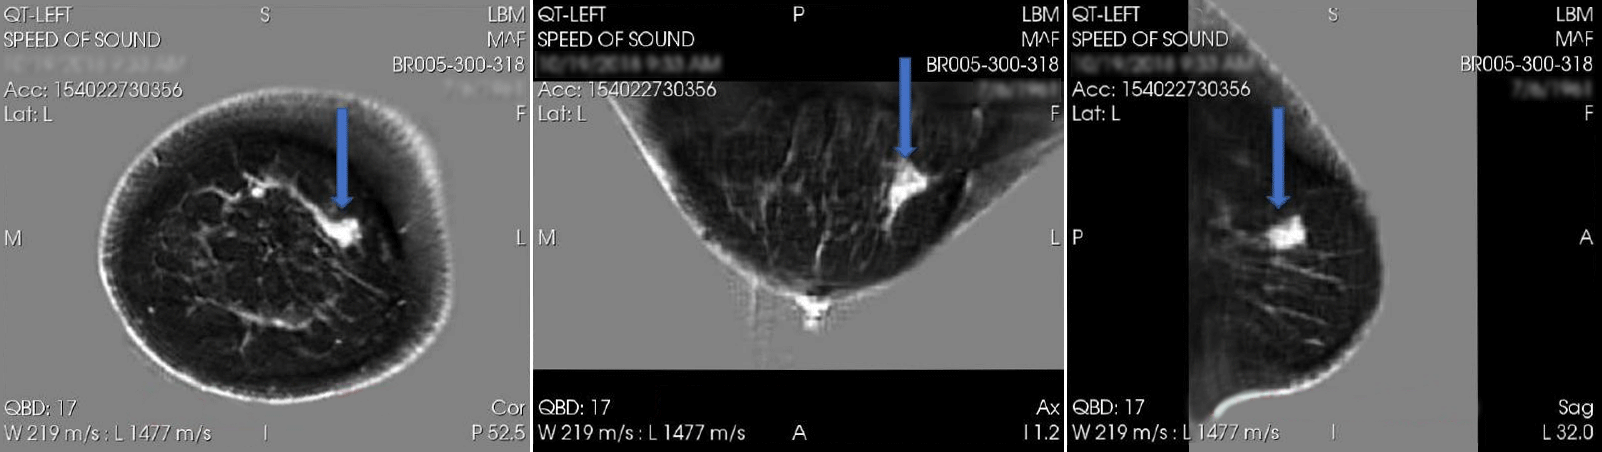

April 16, 2024 — QT Imaging Holdings, Inc., a medical device company engaged in research, development, and commercialization of innovative body imaging systems, announced positive data regarding the diagnostic performance of QTI’s Breast Acoustic CT Scans for mass detection from its second blinded multi-reader multi-case study.